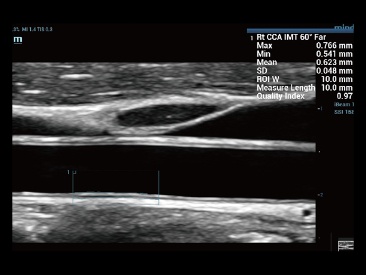

Desde que se fundó la compa?ía, Mindray ha explorado incansablemente nuevas formas de mejorar la confiabilidad del diagnóstico. Con la revolucionaria tecnología de ZONE Sonography?, la nueva plataforma ZST+ de Resona?7 lleva la calidad de la imagen por ecografía a un nivel superior mediante el procesamiento de datos de canal y la adquisición de zona.

Además de la calidad de imagen de primer nivel, Resona?7 también mejora las capacidades de investigación clínica con el revolucionario V?Flow para la evaluación hemodinámica vascular y con la adquisición de planos más inteligente a partir de conjuntos de datos 3D para el diagnóstico del SNC fetal. Al combinar el funcionamiento multitáctil basado en gestos más intuitivo y todas las características clínicas esenciales, Resona?7 realmente lidera las novedades en innovación de ecografías.